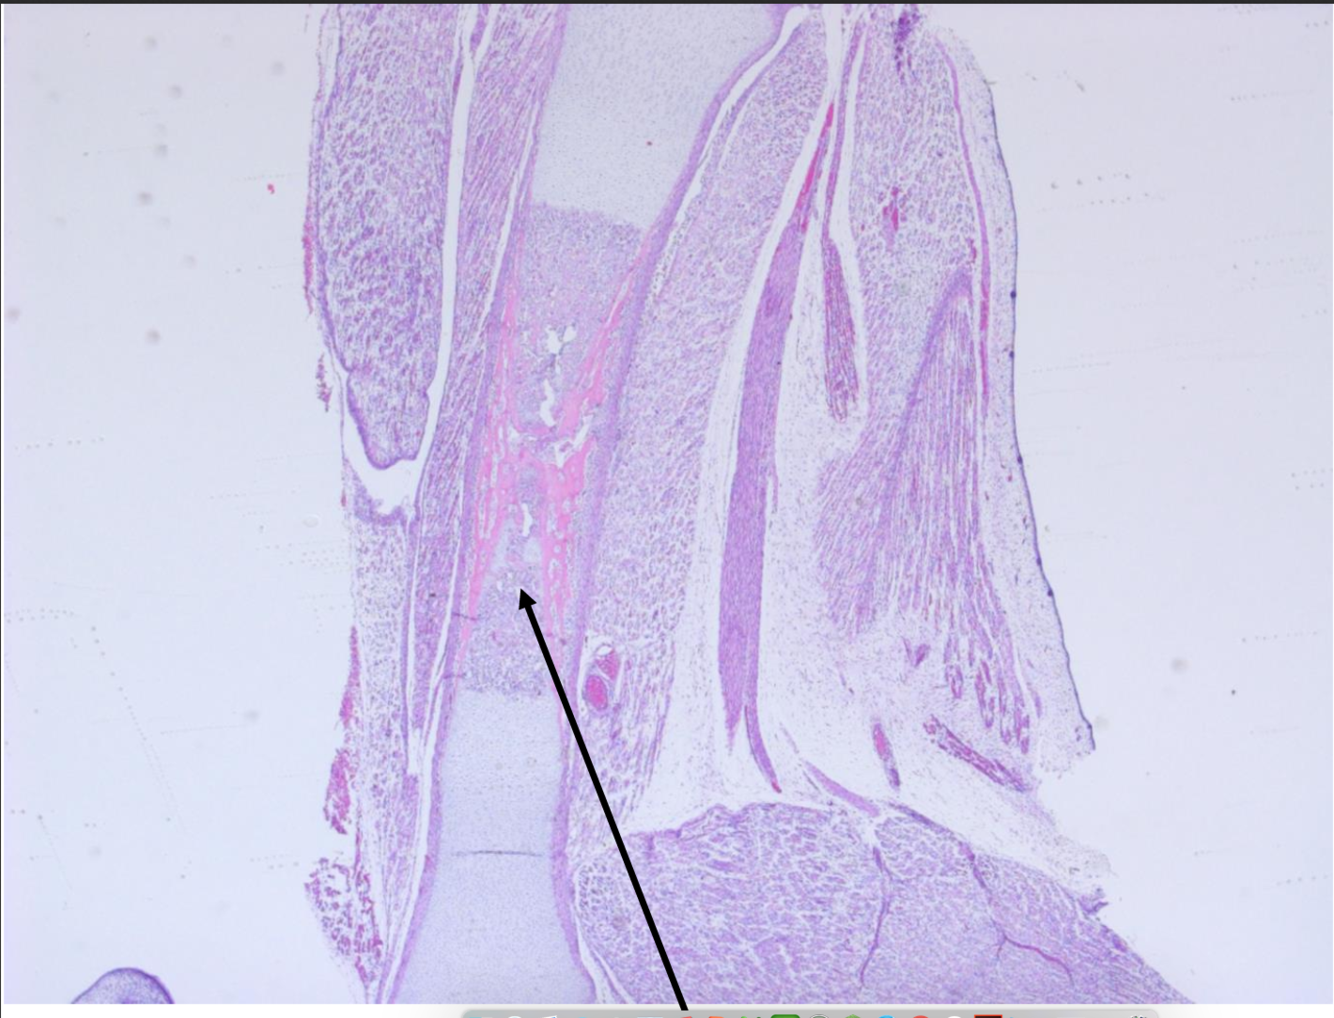

Early periosteal collar formation

Formation of the periosteal collar and early growth plate